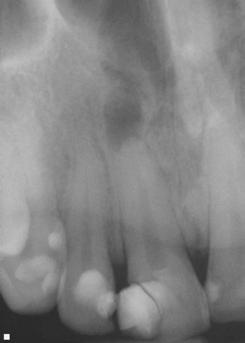

A 56-year-old male presented with a chief complaint of vague discomfort in the left mandible. The patient reported that the discomfort had been intermittent for more than 6 months but

Figures 4A-4H: 4A. Preoperative periapical radiograph of tooth No. 19. Visualization of periapical radiolucency associated with mesial root is possible. Root also appears to be calcified in middle and apical thirds. 4B. Sagittal CBCT slice showing internal resorption in apical portion of mesial root. Visualization of resorptive defect perforating on distal aspect of mesial root, and significant periapical pathology extending close to furcation is possible. Defect and extent of pathology was not visualized on periapical radiograph. 4C. Axial CBCT slice showing resorptive defect encapsulating both MB and ML canals and perforating on distal aspect of mesial root. There is significant bone loss adjacent to perforating defect. 4D. Coronal CBCT slice showing internal resorptive defect encapsulating both mesiobuccal and mesiolingual canals. 4E. Immediate postop radiograph after completion of endodontic treatment. 4F,4G. Coronal and axial CBCT slice at 16-month follow-up. Note resorptive defect filled with bioceramic sealer and complete healing of adjacent bone and reestablishment of PDL. Patient returned at 16-month point for endodontic treatment of tooth No.18. 4H. Three-year follow-up radiograph. Patient remained completely asymptomatic on tooth No 19

had recently worsened. Clinical examination revealed pain to percussion on tooth No. 19. No swelling was observed, and the tooth was not sensitive to palpation or biting. Radiographic and CBCT (Veraviewepocs 3D R100; J. Morita) examination revealed a crowned tooth No.19 with perforating internal root resorption near the apical end of the mesial root, accompanied by periapical pathology extending distally to involve the distal root and coronally toward the furcation (Figures 4A-4D). A diagnosis of pulpal necrosis with symptomatic apical periodontitis was made.

The prognosis for treating the tooth with root canal therapy was discussed, along with alternative options such as extraction and replacement with an implant or bridge. Due to financial constraints, the patient opted for endodontic treatment rather than extraction. It was also explained that follow-up treatment, including an apicoectomy of the mesial root, might be necessary if the lesion persists. Informed consent was obtained.

First visit

The patient was anesthetized with 1.7 mL of 3% mepivacaine (Carbocaine, Dentsply Pharmaceutical, York, Pennsylvania) via left inferior alveolar nerve block and 1.7 mL of 4% articaine with 1:100,000 epinephrine (Septocaine; Septodont, Lancaster, Pennsylvania) via buccal infiltration. After achieving rubber dam isolation, access was made through the porcelain-fused-to-metal (PFM) crown using a combination of a round diamond bur and a No. 2 surgical length carbide round bur. Necrotic pulp was encountered. Working length was established with a Root ZX apex locator (Morita, Tokyo, Japan). The canals were instrumented to a size 35 .04 Vortex Blue rotary file (Dentsply Tulsa Dental, Johnson City, Tennessee) and irrigated with 5.25% sodium hypochlorite. The EndoActivator (Dentsply, Tulsa, Oklahoma) was used to sonically agitate the irrigant to ensure thorough disinfection of the resorptive defect. The canals were dried with paper points, and calcium hydroxide (Ultracal XS, Ultradent Products Inc, South Jordan, Utah) was syringed into the canals and defect. The tooth was then temporarily restored with Cavit (3M ESPE, Neuss, Germany).

Second visit

The patient returned after 3 weeks for completion of endodontic treatment. He reported that all symptoms had subsided. Calcium hydroxide was removed from the canals with instrumentation, irrigation, and activation with the EndoActivator. The canals were dried with paper points, and excess irrigant was removed using a surgical suction with a micro-tip. The canals were coated with BC sealer to allow for sufficient amounts of sealer to fill the resorptive defect and were then obturated with gutta percha and BC (bioceramic) sealer using the technique of warm vertical conden-

sation (Figure 4E). The occlusal access opening was restored with TPH Spectra ST composite (Dentsply Sirona, Charlotte, North Carolina), and the patient was put on a recall schedule to monitor healing. The patient returned at the 16-month point for endodontic treatment of tooth No. 18. At a 16-month recall visit, the patient was completely asymptomatic on tooth No.19. And radiographic/CBCT examination revealed complete healing of the lesion adjacent to the resorptive defect on tooth No. 19 (Figures 4F and 4G). At the 3-year recall, the patient was asymptomatic on both teeth Nos.18 and 19.